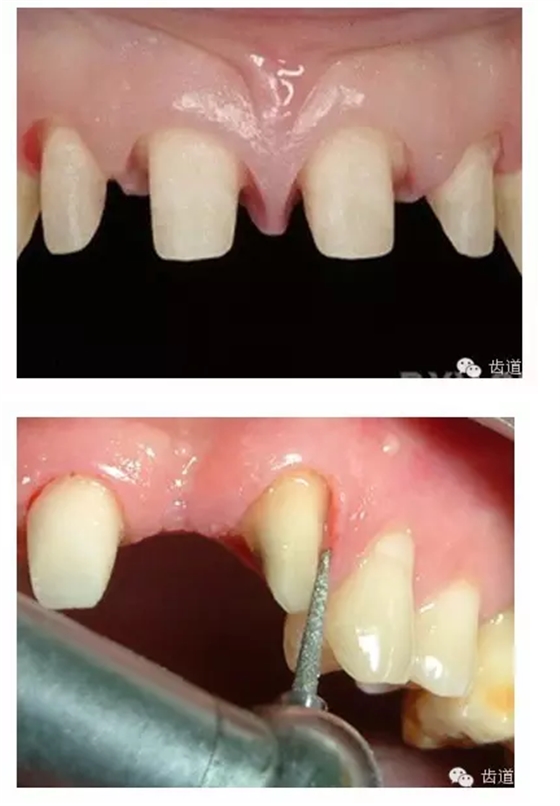

l實(shí)際備牙產(chǎn)生的問(wèn)題

l防止過(guò)度預(yù)備(造成牙髓激惹)

l保留活髓(保留牙體的整體性和韌性)

l過(guò)度預(yù)備抗力形喪失